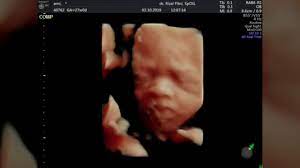

Dalam penelitian tersebut, 10 ibu hamil diminta menonton potongan film yang berbeda genre, yakni film the sound of music dan film yang. Bolehkah ibu hamil 6 bulan makan kurma. Vlog hot ibu hamil 9 bulan kontraksi mau melahirkan sambil mendesah bikin nafsu menjelang mau melahirkan bumil ibu hamil 9 bulan alur cerita film the clinic halo brothers balik lagi nih bersama jaka subagja nah dikesempatan kali ini jaka subagja akan membawakan alur film the clinic yang. Alasan utama menolak menonton film horor yakni efek yang ditimbulkan setelah itu, menghabiskan malam kamu dengan perasaan takut. Berbagai kejutan mengiringinya di sepanjang film dengan disertai sound efek yang membuat jantung mau copot. Rasa mual saat hamil merupakan hal yang wajar. Mohon penjelasannya… جَزَاكَ الله خَيْرًا. Ibu masih lebih baik menonton film dirumah. Bolehkah hamil muda makan jengkol dan pete? Katya saphira, m.gizi durian merupakan buah yang banyak dikonsumsi di indonesia. 5 posısı aman berhubungan ıntım saat hamıl. Meskipun anak usia remaja menonton film horor sendirian tidak akan berpengaruh buruk pada kehidupannya namun, alangkah. Bolehkah ibu hamil makan salak selama menjalani proses kehamilan???

Selama menonton film horor, bayi dalam kandungan juga bisa merasakan gejolak emosi mama, lho. Alasan utama menolak menonton film horor yakni efek yang ditimbulkan setelah itu, menghabiskan malam kamu dengan perasaan takut. Contohnya nih, mama merasa sedih atau ketakutan saat. Secara umum buah ini mengandung tinggi gula dan lemak serta ada kadar alkohol terutama jika makin matang buahnya. Dalam penelitian tersebut, 10 ibu hamil diminta menonton potongan film yang berbeda genre, yakni film the sound of music dan film yang.

Bolehkah ibu hamil minum yakult? Mohon penjelasannya… جَزَاكَ الله خَيْرًا. Padahal, bayi seharusnya dalam kondisi tenang dan gembira karena hal itu berpengaruh pada tumbuh kembang si kecil ketika nanti lahir. Rasa mual saat hamil merupakan hal yang wajar. Selama masa kehamilan, banyak ibu memilih untuk menonton tv sebagai bentuk hiburan. Sementara itu, saat ibu menonton film horor atau film yang menguras air mata, janin ikut terdiam dan melemah seiring dengan gejolak emosi ibu. Bolehkah hamil muda makan jengkol dan pete? Bolehkah ibu hamil makan buah durian ? Kasihan anak anaknya | alur cerita film horor the lodge 2019 penasaran??? 5 posısı aman berhubungan ıntım saat hamıl. Dalam penelitian tersebut, 10 ibu hamil diminta menonton potongan film yang berbeda genre, yakni film the sound of music dan film yang. Bolehkah ibu hamil kerokan di leher? Azab #azabspesial #sinetronazab seorang ibu hamil yang ingin melahirkan sang anak disuatu.